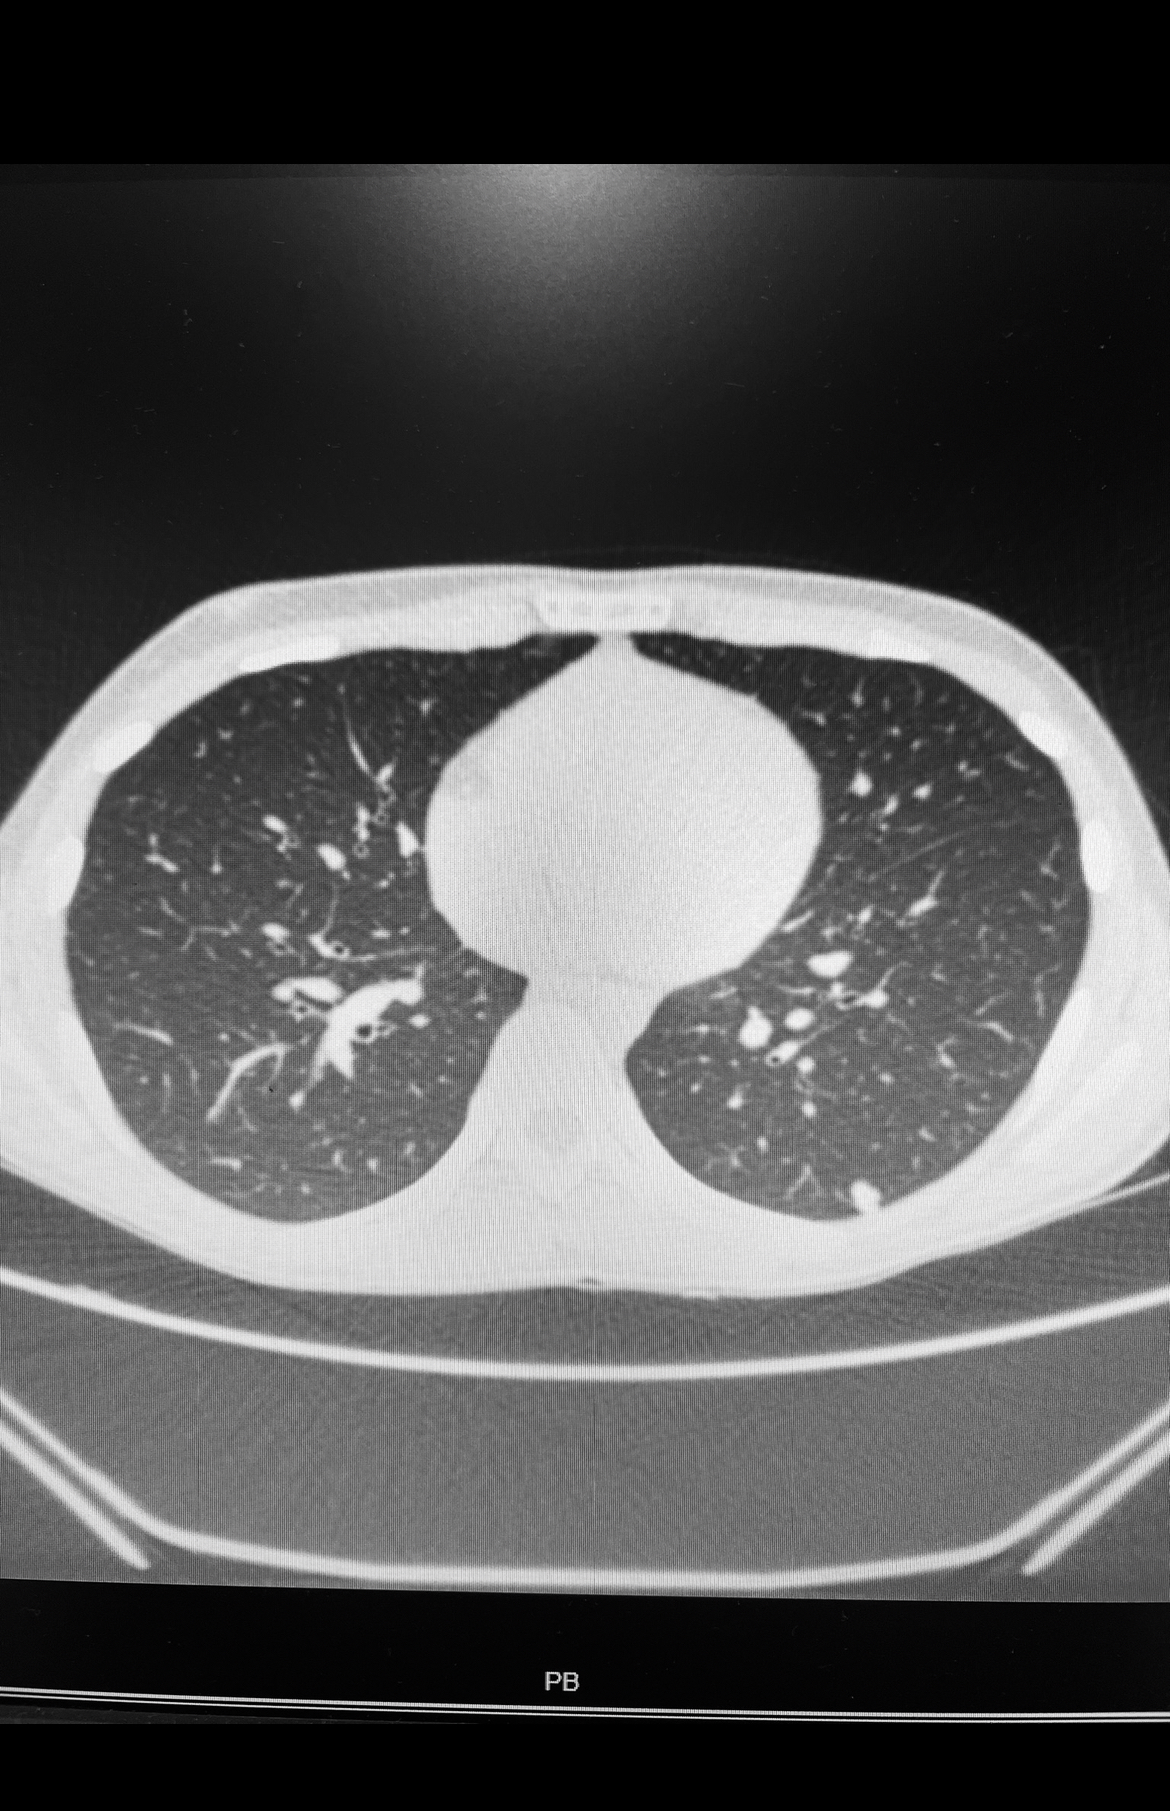

Tras el diagnóstico de una sarcoma de partes blandas, confirmado por la biopsia, se debe realizar un estadiaje con un TC de tórax. El objetivo es descartar una posible metástasis pulmonar. El pulmón es la localización mas frecuente de metástasis de los sarcomas de partes blandas. En algunos subtipos de sarcomas de partes blandas se pueden también solicitar un PET-TAC, una gammagrafía ósea, y/o una resonancia magnética de cuerpo entero.

TC de tórax con metástasis pulmonar en lóbulo inferior izquierdo